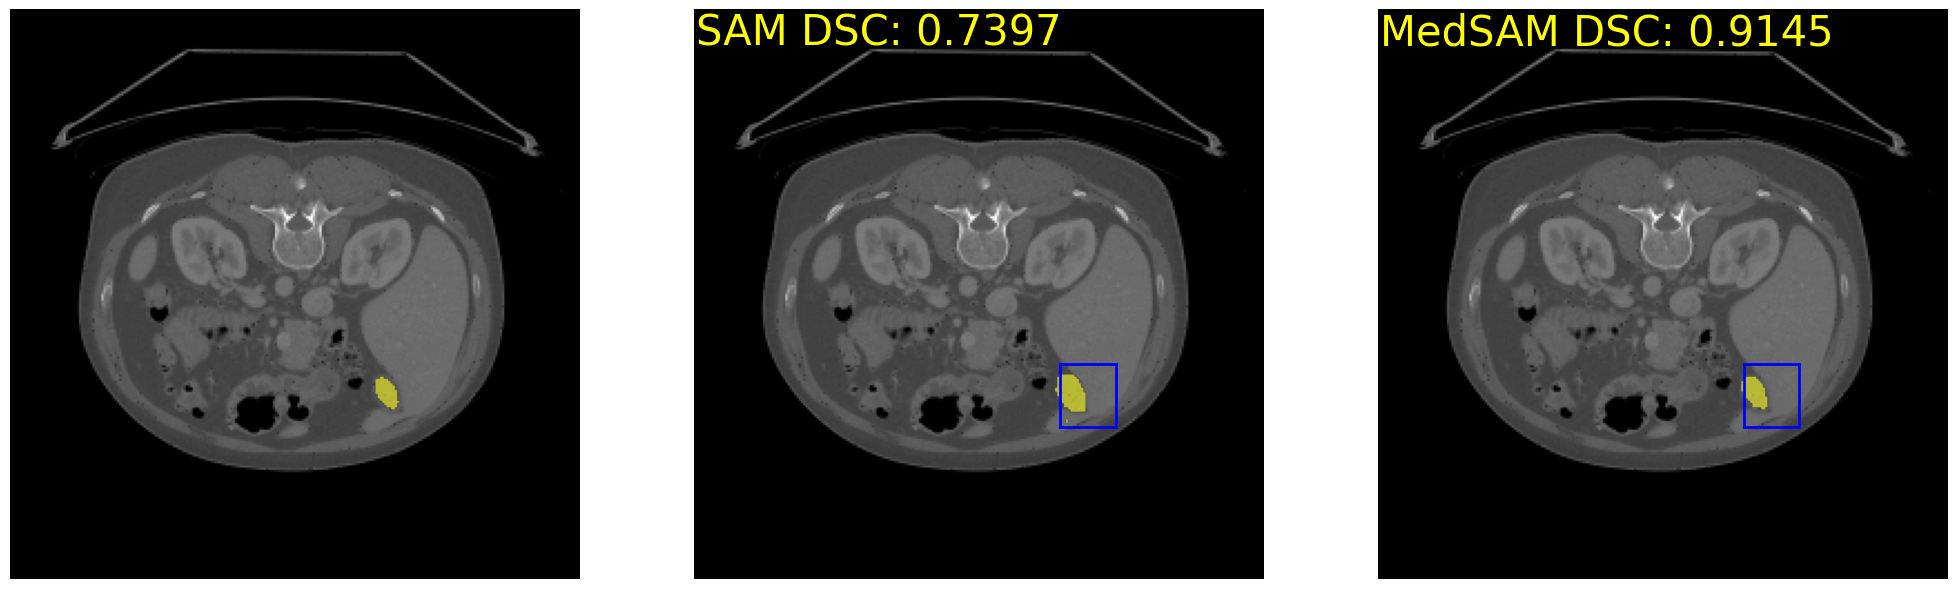

print('Original SAM DSC: {:.4f}'.format(ori_sam_dsc), 'MedSAM DSC: {:.4f}'.format(medsam_dsc))Original SAM DSC: 0.7397 MedSAM DSC: 0.9145

_, axs = plt.subplots(1, 3, figsize=(25, 25))

axs[0].imshow(image_data)

show_mask(gt_data>0, axs[0])

axs[1].imshow(image_data)

show_mask(ori_sam_seg, axs[1])

show_box(bbox_raw, axs[1])

axs[1].text(0.5, 0.5, 'SAM DSC: {:.4f}'.format(ori_sam_dsc), fontsize=30, horizontalalignment='left', verticalalignment='top', color='yellow')

axs[2].imshow(image_data)

show_mask(medsam_seg, axs[2])

show_box(bbox_raw, axs[2])

axs[2].text(0.5, 0.5, 'MedSAM DSC: {:.4f}'.format(medsam_dsc), fontsize=30, horizontalalignment='left', verticalalignment='top', color='yellow')